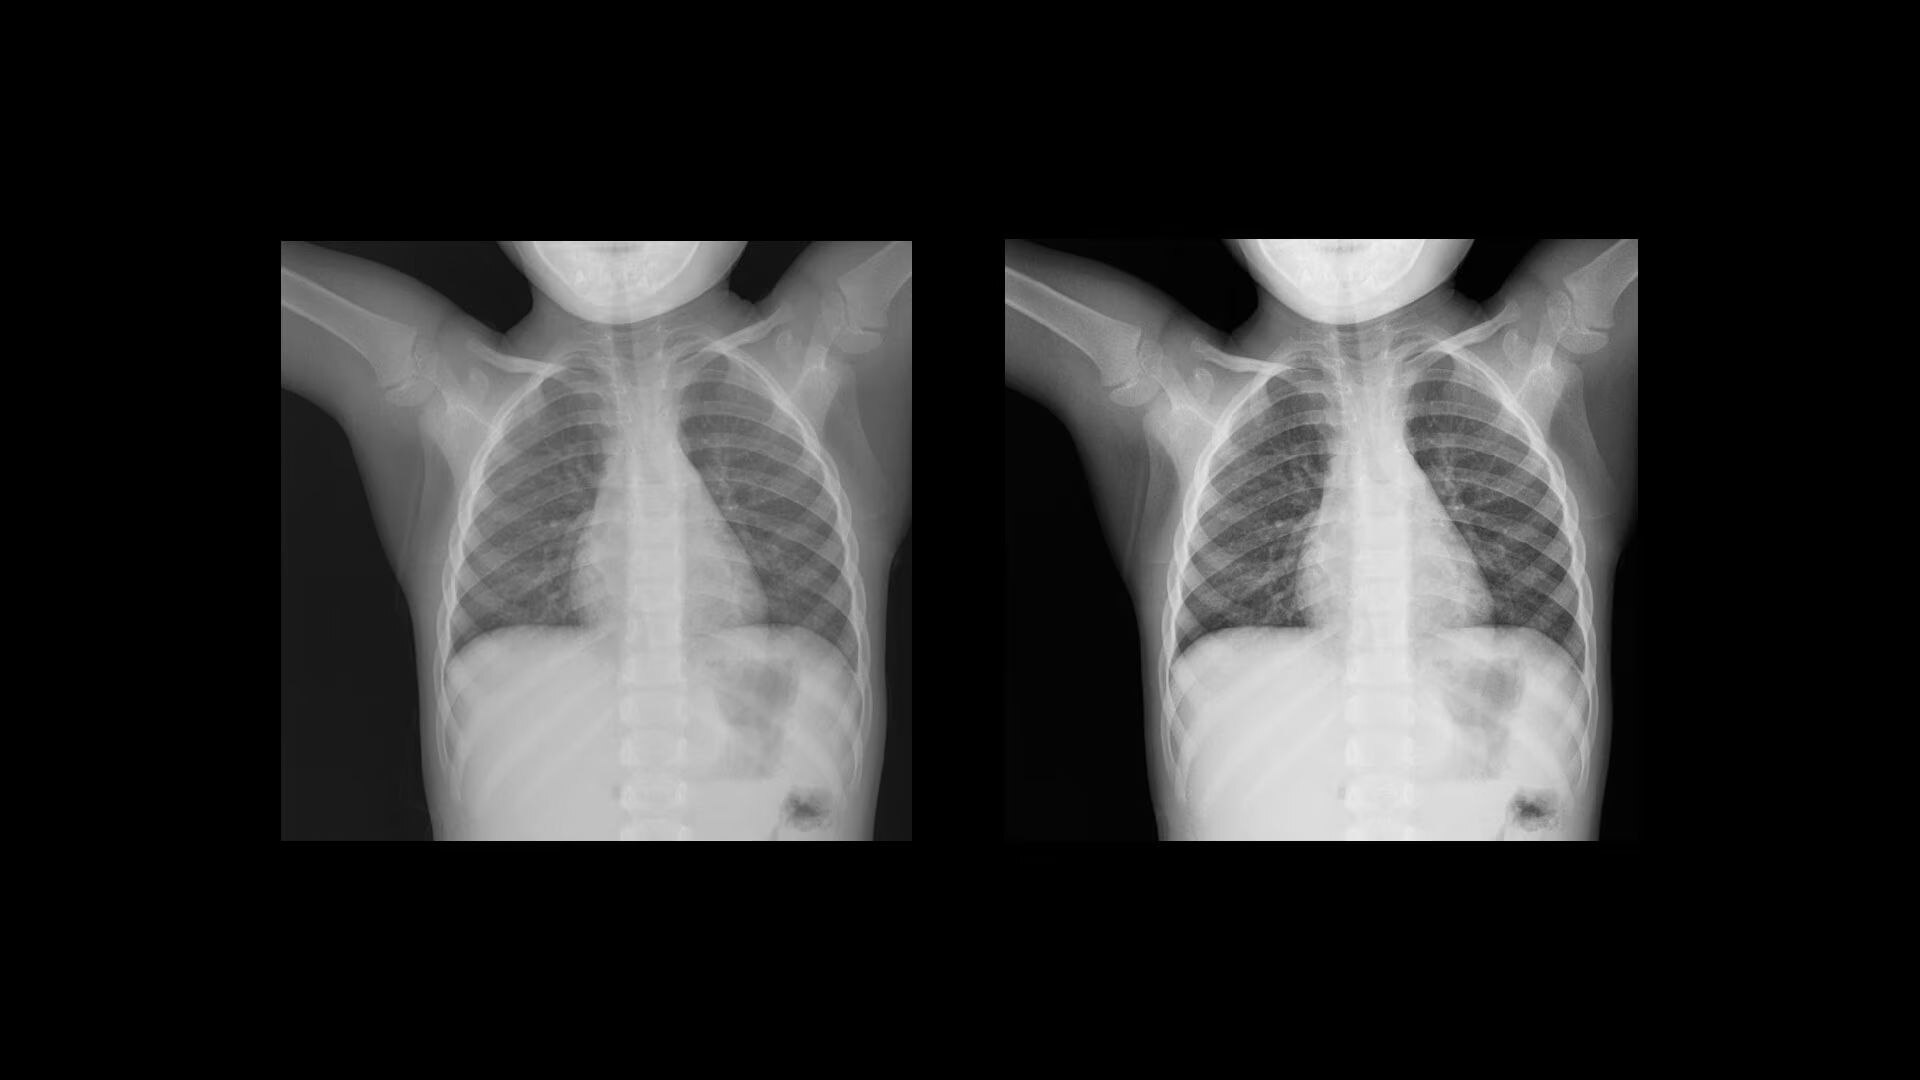

Clarity

Improve visualization and detail

Local Contrast Enhancement (LCE) increases local contrast in both pediatric and adult chest X-ray images for better visualization of the lungs, heart, and spine regions. It is also available for ankle joint (AP), foot (AP), and patella (tangential)*, and has three levels of enhancement (low, medium and high).